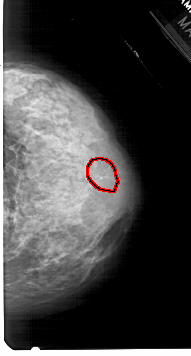

RIGHT_MLO LINES 5461 PIXELS_PER_LINE 2836 BITS_PER_PIXEL 12 RESOLUTION 43.5 OVERLAY

FILE: A_1935_1.RIGHT_MLO.OVERLAY

TOTAL_ABNORMALITIES 1

ABNORMALITY 1

LESION_TYPE CALCIFICATION TYPE PLEOMORPHIC DISTRIBUTION CLUSTERED

ASSESSMENT 4

SUBTLETY 4

PATHOLOGY BENIGN

TOTAL_OUTLINES 1

BOUNDARY